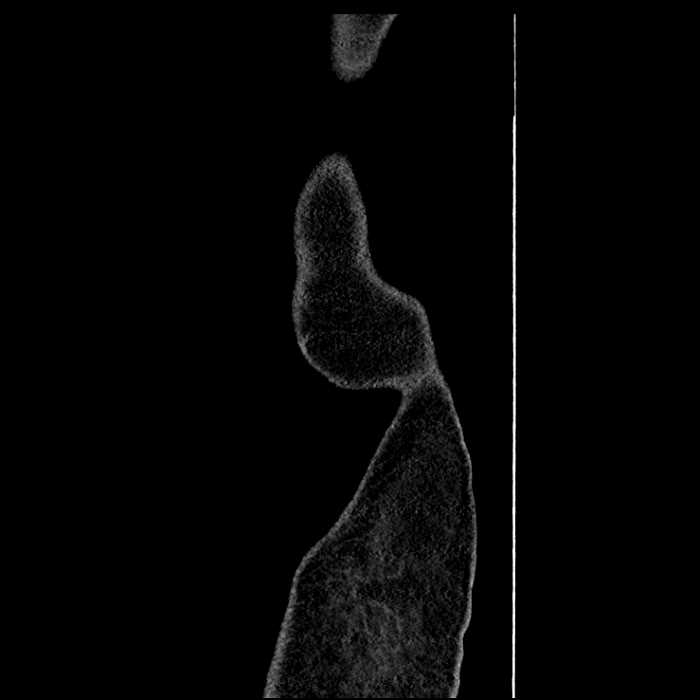

• High grade stenosis of the left common iliac artery, with the left internal and external iliac arteries remaining patent

High grade stenosis of the left common iliac artery. The left external and internal iliac arteries are patent.